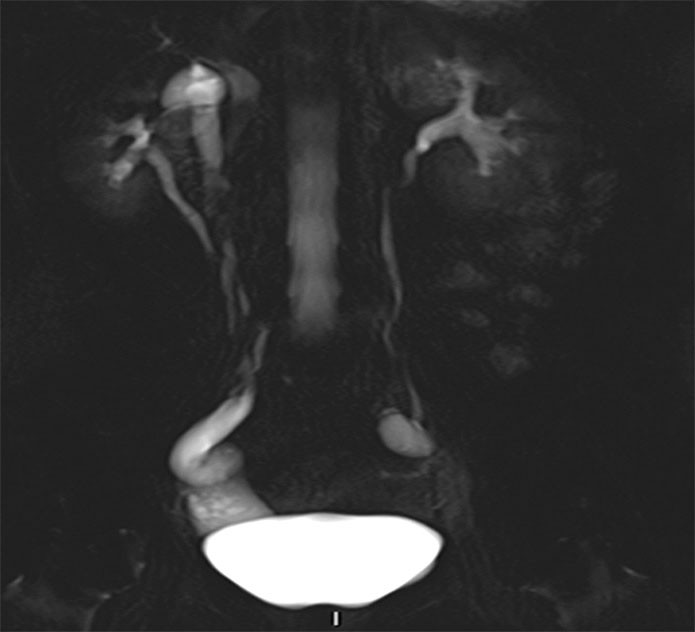

A CT scan of the urinary tract was performed, but proved inconclusive with respect to ureteral ectopia. MRI of the urinary tract was therefore performed in addition. This revealed a right-sided duplex collecting system with a small upper collecting system and a dilated ureter (Figure 1). The ureter was dilated from the bladder to the vagina and opened out ectopically near the urethral opening (Figure 2).

Figure 2 MRI. Transverse 3D section with high resolution T2 weighting shows a right-sided dilated ectopic ureter.

Identification of a duplex collecting system and ectopic ureter on CT requires adequate function and contrast excretion from the upper collecting system, which was not the case in this patient. It is possible to detect a dilated ectopic ureter with ultrasound, but this can be difficult unless the condition is specifically looked for. Our patient was referred with suspected cholelithiasis and pyelonephritis, and no pathology was detected upon routine examination of the urinary tract. High-resolution fluid-sensitive volumetric MRI sequences are good for identifying the ureter and tracing its course. MRI is more appropriate than CT in the lesser pelvis, but more time-consuming. Dedicated high-resolution series in the pelvis were supplemented with less detailed sequences of the upper urinary tract. No contrast agent was used during the MRI scan. Paediatricians use MRI as the primary imaging modality upon suspicion of ureteral ectopia.